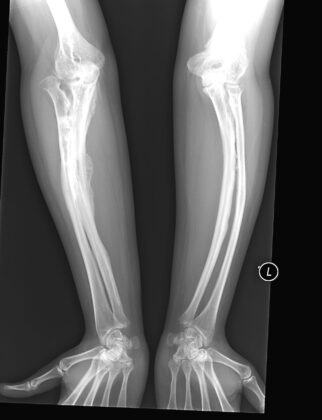

Drengurinn var að verða tveggja ára gamall, þegar að sunnlenskir læknasérfræðingar komumst loksins að þeirri niðurstöðu að hann væri fæddur með alvarlegan beinþynningar sjúkdóm sem heitir: Osteogenesis imperfecta (OI) og honum geta fylgt ýmsir aukakvillar.

Bogin bein og gömul gróin beinbrot.

Móðirin var tíður gestur á Sjúkrahúsi Siglufjarðar og læknum tókst ekki að finna á þessu nokkra læknisfræðilegar útskýringar. Þegar hann byrjaði að skríða, brotnuðu á honum fingur og tær og seinna þegar okkar manneskjulega þörf kom yfir hann, við að reyna að standa uppréttur og ganga, var eins og að fæturnir bognuðu undir blessuðu barninu og varð hann þar af snemma mjög svo hjólbeinóttur og líktist göngulagið mest gömlum hestabónda. Í þessum barnalegu tilþrifum sínum við það eitt að reyna að ganga, datt hann oft og það kostaði hann bæði handleggs og handliðsbrot, með tilheyrandi gifsumbúðum.

Gurrý beinþynningar sérfræðingur veit mikið vel að í dag eru til bæði skurðaðgerðar lausnir sem rétta upp bogin bein og lyf sem styrkja þessi brothættu bein. Hún sér einnig fyrir sér tíðarandann, sem ræður ríkjum þegar þessi læknisfræðilegu ráð eru gefinn og að hún sem og móðir hennar, í umhyggjusamri velvild og hræðslu við að missa blessað barnið frá sér, sköpuðu þetta of verndaða, ófrjálsa og einangraða líf sem bróðir hennar var tilneyddur að lifa.